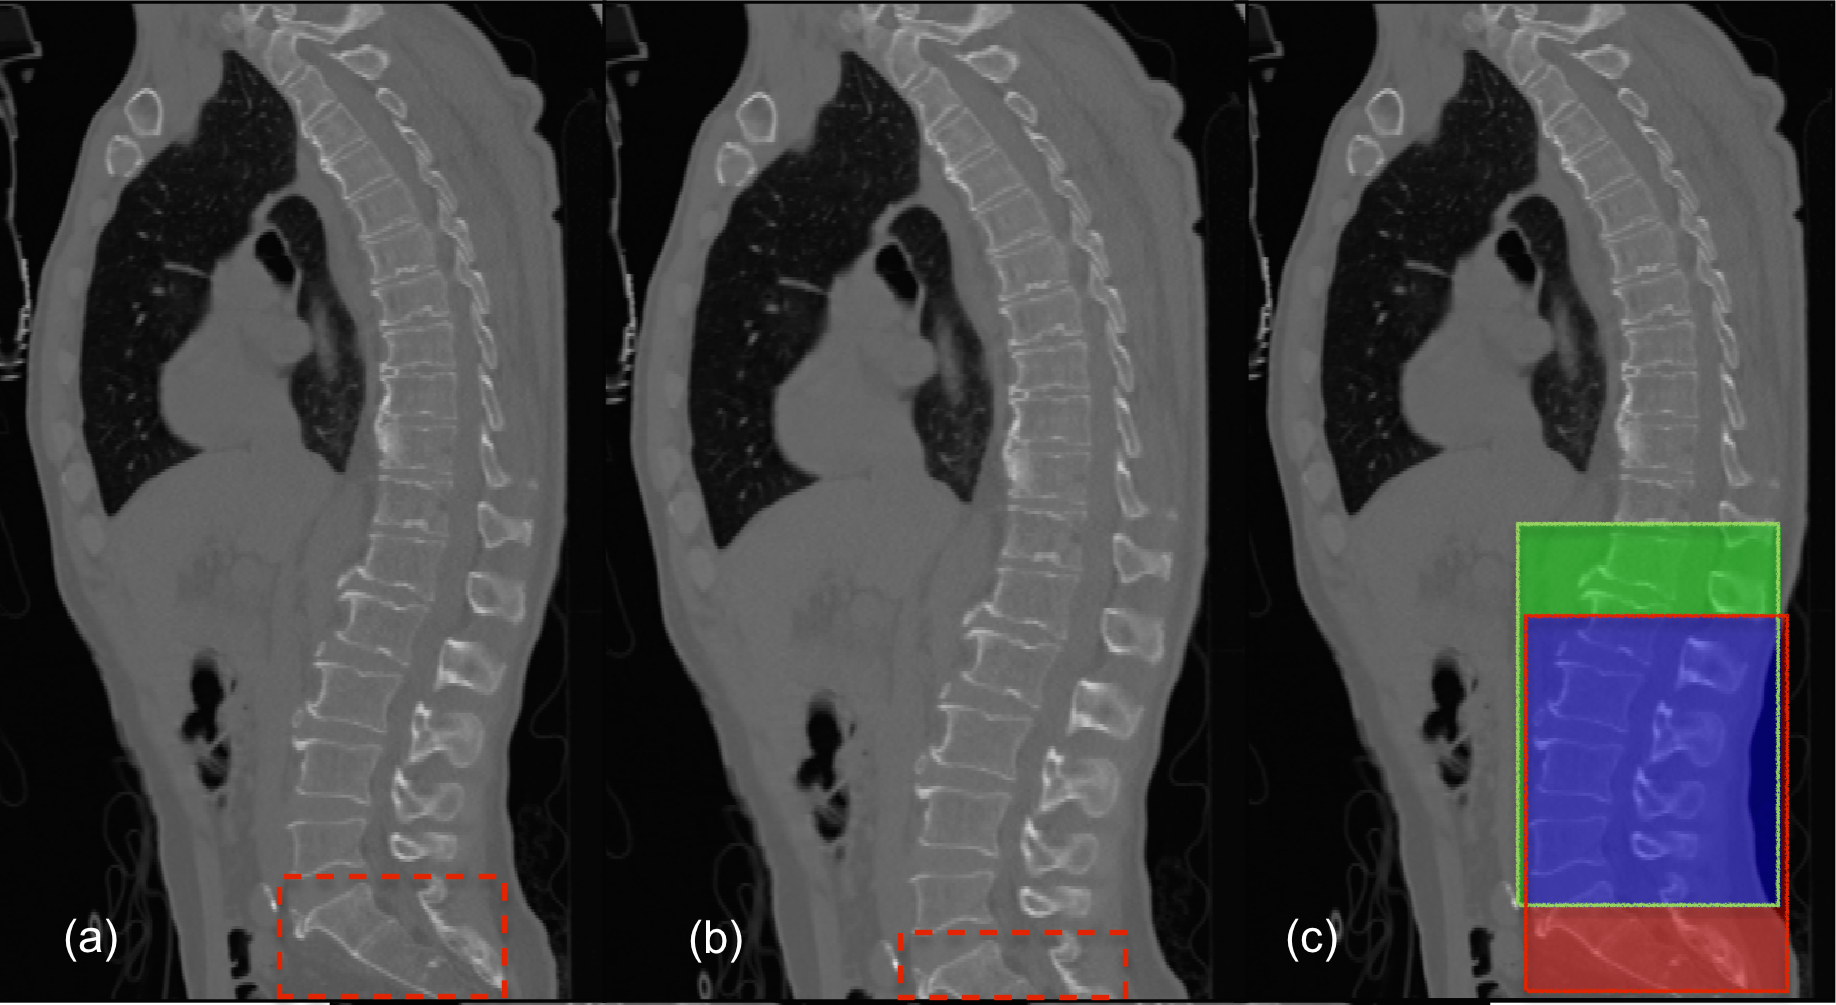

Each pass through the regressor using a feature corresponding to a certain voxel predicts the locations of the bounding planes with respect to that voxel. In order to speed-up the feature generation procedure without loss of useful information, only the significant voxels are considered for feature extraction. For this purpose, the voxels from the response of a Canny’s edge detector are used for feature extraction. Thus, every significant voxel votes for a prospective bounding box of which the most representative bounding box is chosen. Figure 2 shows a few examples of the localised lumbar regions.

Refer to caption

Figure 2: Lumbar Localisation: The axial, sagittal, and coronal views of the bounding box localising the lumbar section. (Row 1) Case 18 containing severe abnormalities such as multiple fractures and scoliosis is localised perfectly. (Row 2) Case 22 shows a mild under-localisation, not localising a top region of L1.

To measure the performance of localisation, a measure of sensitivity (or true positive rate) was used, as defined: S=1|𝒢c||𝒢|,𝑆1𝒢superscript𝑐𝒢S=1-\frac{|\mathcal{G}\cap\mathcal{B}^{c}|}{\mathcal{|G|}}, where 𝒢𝒢\mathcal{G} is the of set voxels in the ground truth segmentation, and \mathcal{B} is the set of voxels within the bounding box. We use the ground truth segmentation for Rater-1 for this purpose. The sensitivity measures on the test set are shown in table 1, with a few cases shown visually in figure 2. We obtain a near perfect localisation of 1.0 in all cases except one (Case025). In order to completely cover the lumbar region, a tolerance of 15 voxels is added to the bounding boxes on all sides before considering the localisation for for the next stage.